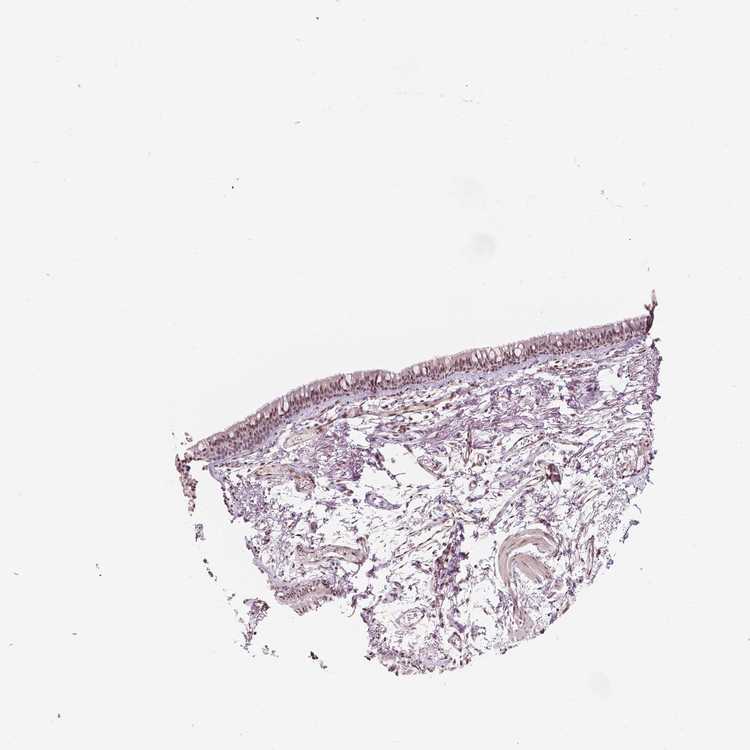

TISSUE PRIMARY DATA SOFT TISSUE Show tissue menu

SOFT TISSUE - Expression summary

SOFT TISSUE 1 - Antibody stainingi

Antibody staining in the annotated cell types in the current human tissue is reported as not detected, low, medium, or high, based on conventional immunohistochemistry profiling in selected tissues. This score is based on the combination of the staining intensity and fraction of stained cells.

Each image is clickable and will lead to virtual microscopy that enables deeper exploration of all samples and also displays staining intensity scores, fraction scores and subcellular localization as well as patient and tissue information for each sample.

Antibody HPA042128Antibody HPA049883Antibody HPA051156Antibody CAB004298

Chondrocytes Not detectedNot detected--

Fibroblasts Not detectedNot detectedLowMedium

Peripheral nerve Not detected---